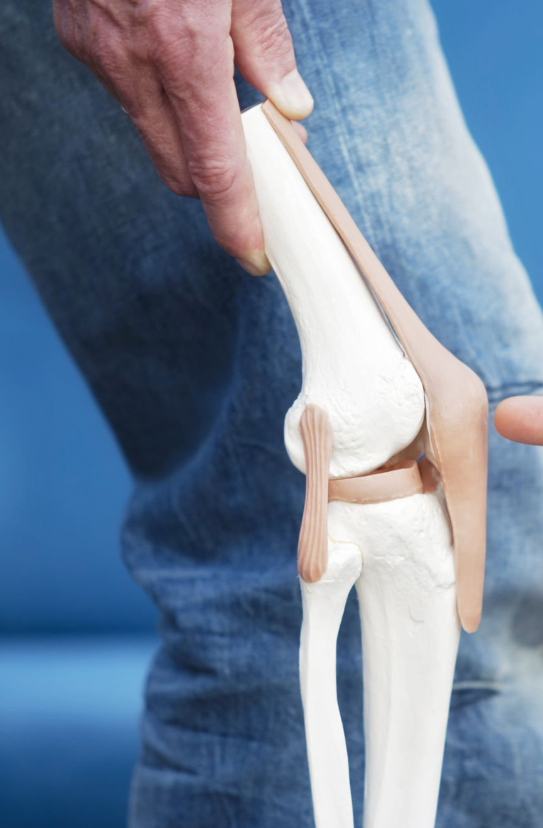

관절 통증과 연골 손상은 나이가 들면서 많은 사람들이 겪는 일반적인 문제들입니다.

콘드로이친은 특별히 이러한 문제를 경감시키는 데에 큰 도움이 되는 물질로 손꼽히며, 주요 구성 성분으로는 연골 내에 존재하는 글리코사미노글리칸의 하나입니다.

콘드로이친 섭취의 주된 이점은 관절염 관리와 통증 경감에 있습니다.

콘드로이친은 연골 내 수분을 유지하고, 이로 인해 연골이 쿠션 역할을 더 잘 할 수 있도록 돕는다고 알려져 있습니다.

따라서 관절과 뼈 사이의 마찰을 줄여주어 관절염으로 인한 통증과 뻣뻣함을 완화시킬 수 있습니다.

뿐만 아니라 연골의 깊은 부위에 영양을 공급하여 연골의 손상을 회복하고 연골세포의 신진대사를 촉진하는 역할도 합니다.